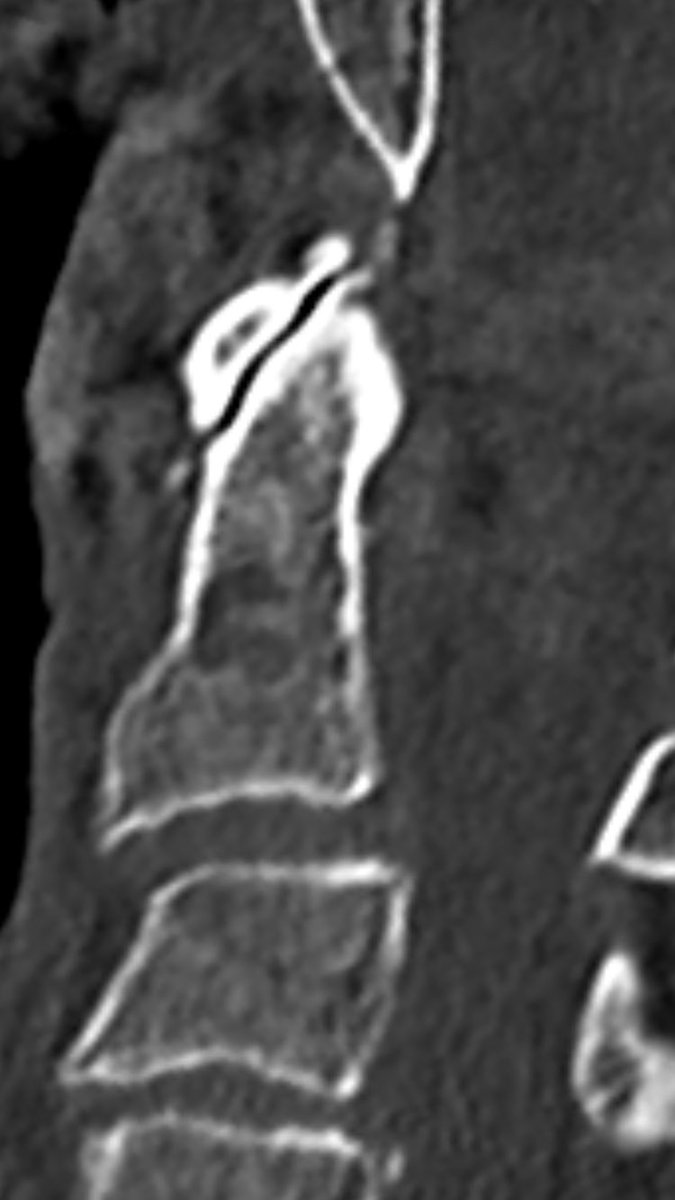

follow up after 8 weeks (l) and 6 month (r) show non-union, as expected. It’s a pseudarthosis.

You can nicely see signs of remodelling, but the fracture line still remains.

after 16 month, remodelling is still ongoing: surprisingly the atlantodental joint is now ankylosed and the fracture line is narrowed, but still not fused.

(CT was performed for other reason)